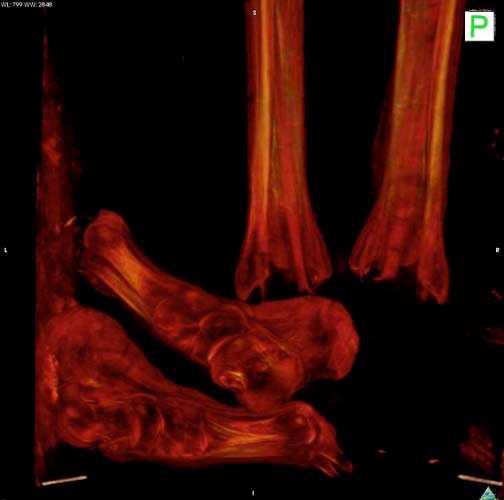

2. Fotoğrafta gördüğünüz Mısır mumyasının CT taraması, uygarlığının gizemlerini çözmeye yardımcı olacak.

Fotoğrafta gördüğünüz Mısır mumyasının CT taraması, uygarlığının gizemlerini çözmeye yardımcı olacak.

3. İngiltere'de Dr. Abeer Helmi, bu teknolojiyi kullanarak tarihin derinliklerinden gelen lahitleri açarken zarar verme riski olmadan içeriğini görüntüleyebiliyor.

İngiltere'de Dr. Abeer Helmi, bu teknolojiyi kullanarak tarihin derinliklerinden gelen lahitleri açarken zarar verme riski olmadan içeriğini görüntüleyebiliyor.

4. Dr. Helmi, British Museum'dan özel izinle aldığı yedi mumya üzerinde bu cihazı test etti.

Dr. Helmi, British Museum'dan özel izinle aldığı yedi mumya üzerinde bu cihazı test etti.

5. Yapılan taramalar M.Ö. 900 civarında Mısırlıların sağlığı ve davranışları konusunda önemli ipuçları verdi.

Yapılan taramalar M.Ö. 900 civarında Mısırlıların sağlığı ve davranışları konusunda önemli ipuçları verdi.